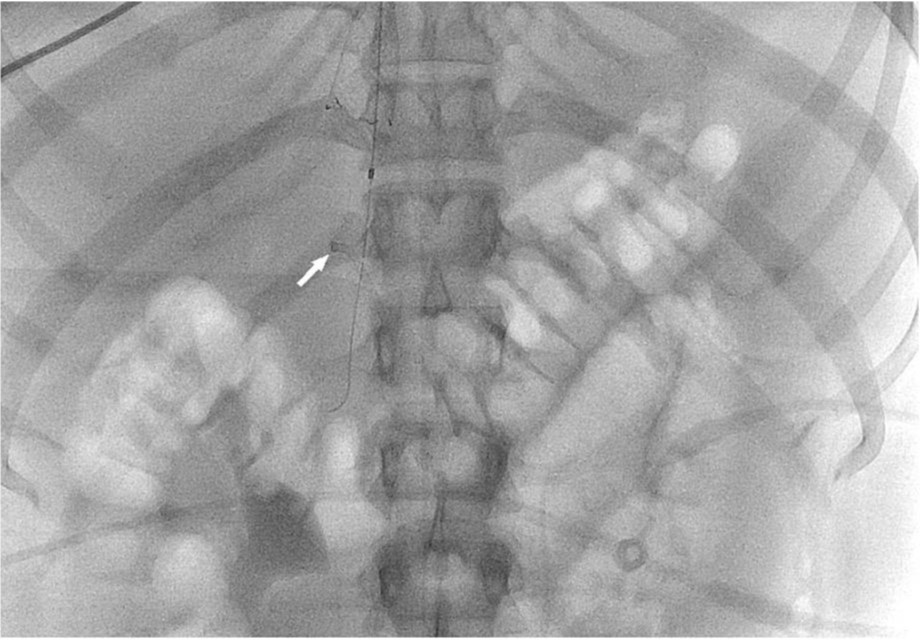

Fig. 2. A

Fig. 2. A. IVC venogram shows large filling defect due to thrombus.